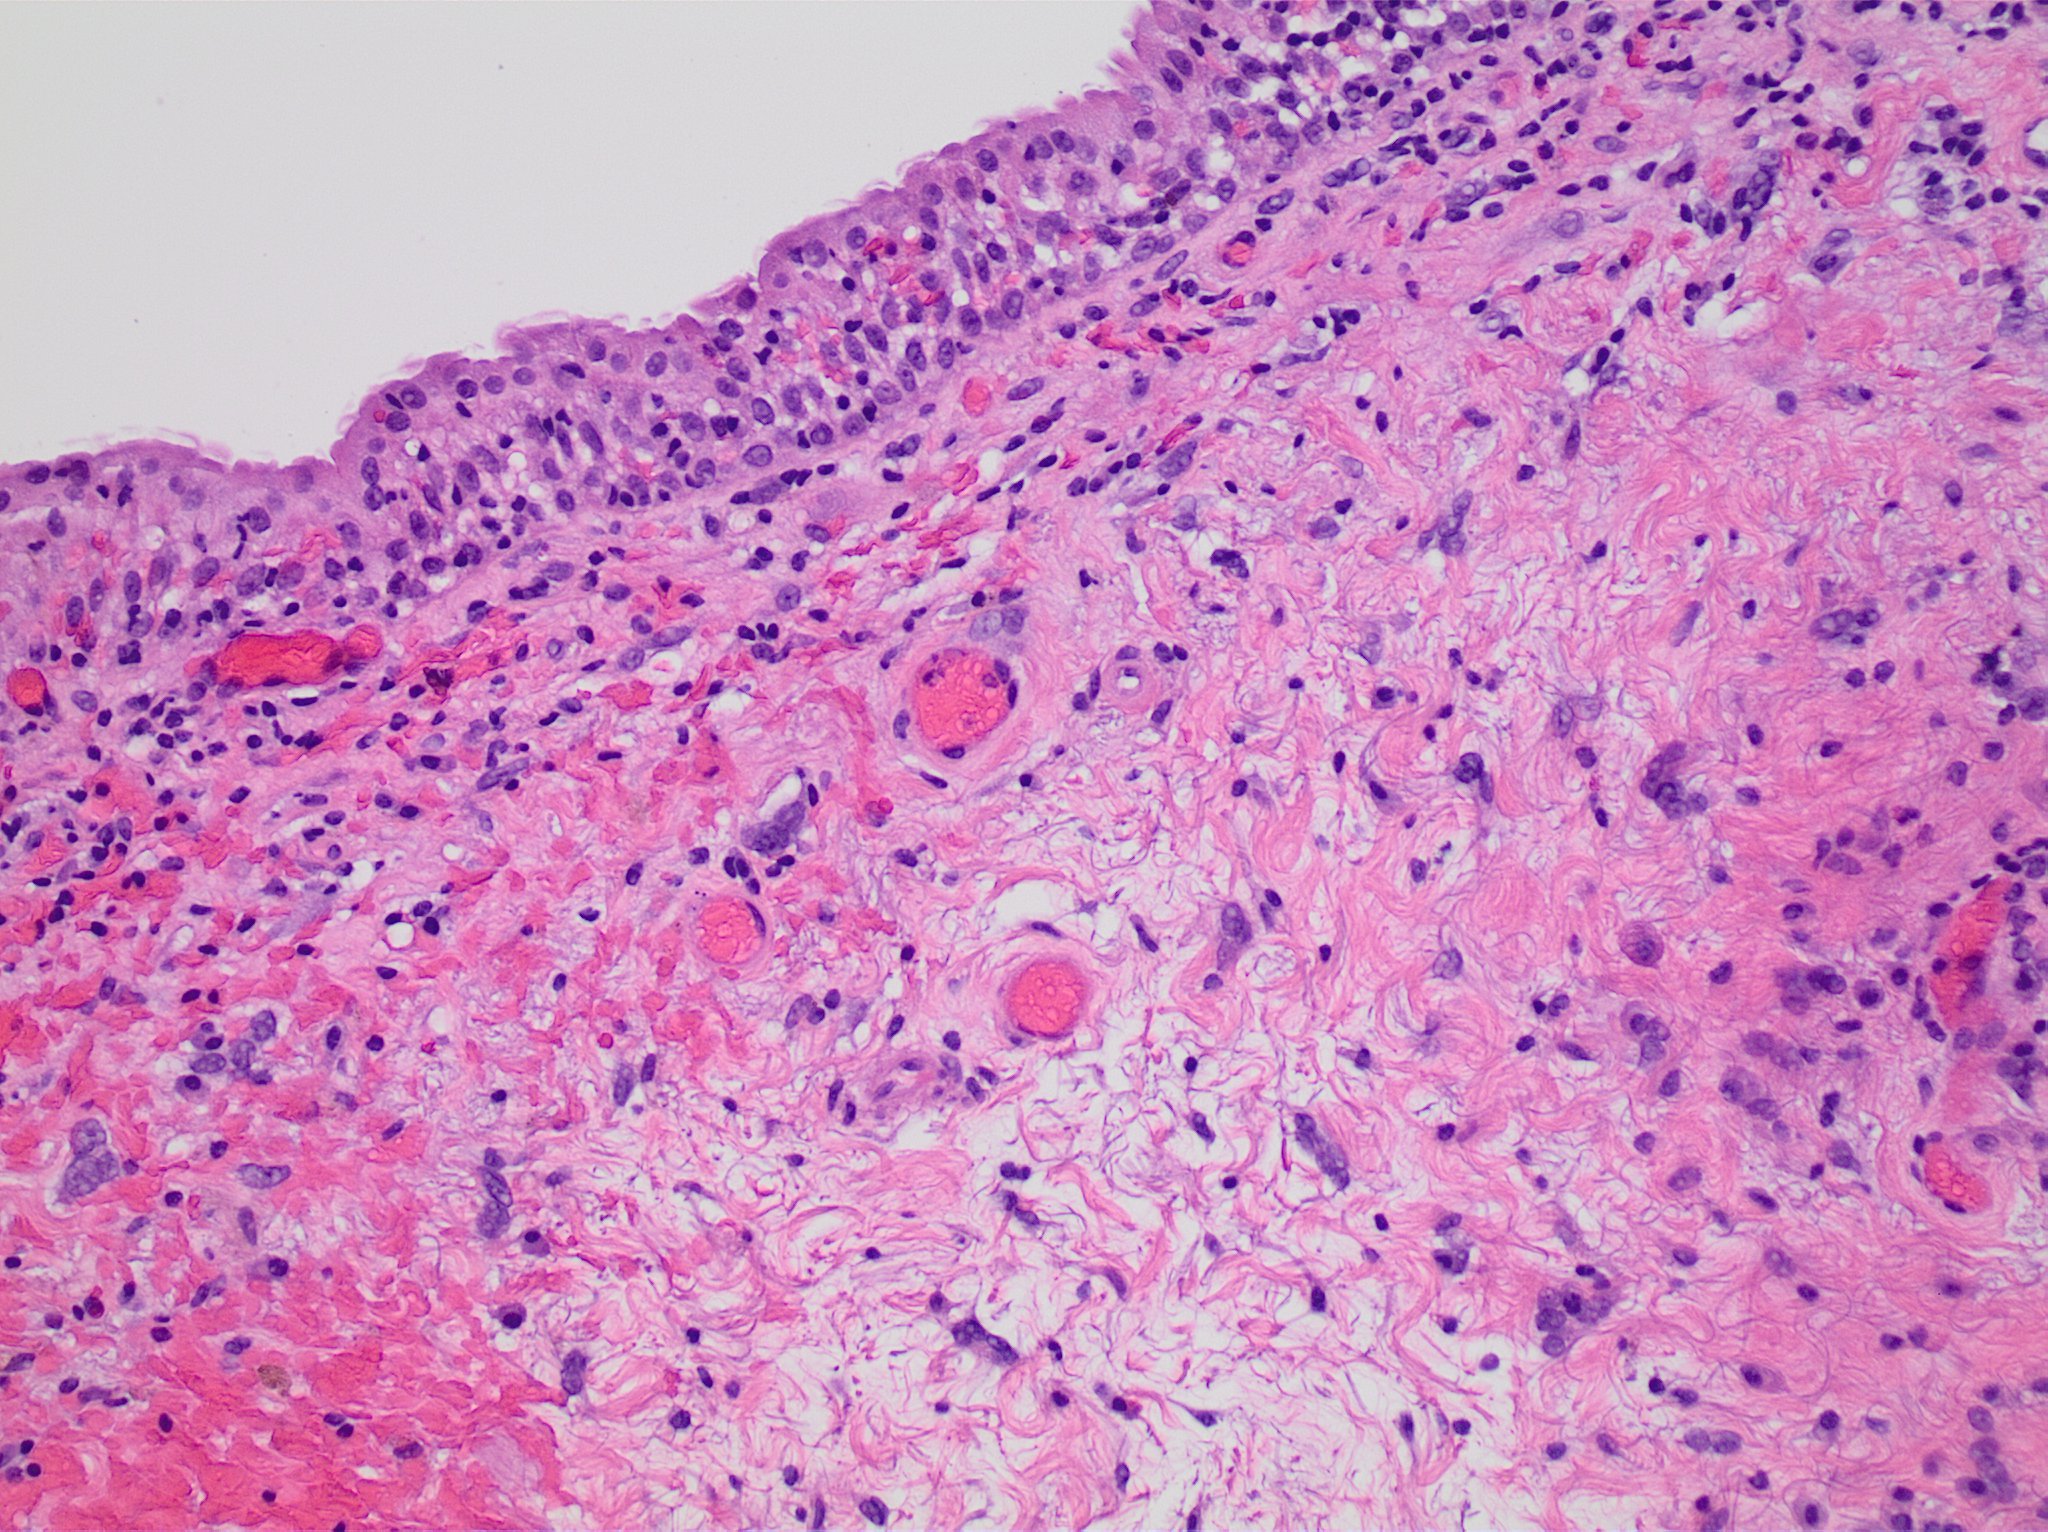

상피 조직은 방사선 치료로 인해 손상될 수 있다.[167] 치료 부위에 따라 피부, 구강 점막, 인두, 장 점막, 요관 등이 포함될 수 있다. 손상 시작과 회복 속도는 상피세포의 회전율에 따라 달라지는데, 일반적으로 피부는 치료를 시작한 지 몇 주 만에 분홍색으로 변하고 아프기 시작한다. 치료 중과 방사선 치료 종료 후 일주일 동안 반응이 더욱 심해져 피부가 벗겨질 수 있다. 이러한 습윤성 박탈은 불편하지만 회복은 일반적으로 빠르다. 피부 반응은 여성의 유방 아래, 귀 뒤, 사타구니와 같이 피부에 자연스러운 주름이 있는 부위에서 더 심해지는 경향이 있다.[19]5. 1. 2. 입, 목, 위 염증

5. 2. 1. 섬유증

방사선 조사 부위는 확산 흉터 형성 과정을 거치면서 시간이 지남에 따라 조직이 굳어지고 탄력을 잃는 섬유증이 발생할 수 있다.5. 2. 2. 탈모